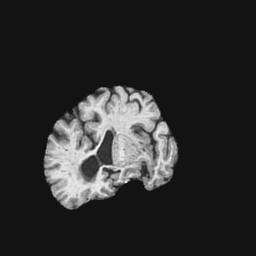

Exp. 1: Segmented adult brain data is used to evaluate our network’s regression performance with known ground truth . 85 brains from the ADNI data set[1] were randomly selected; 70 brains for and 15 brains for . Fig. 2 shows an example slice of the ground truth and the reconstructed .

Reconstructing from initialisation without SVR yields a PSNR of 23.7 1.09; with subsequent SVR the PSNR increases to 29.52.43 when tested on 15 randomly selected test volumes after four iterations of SVR.